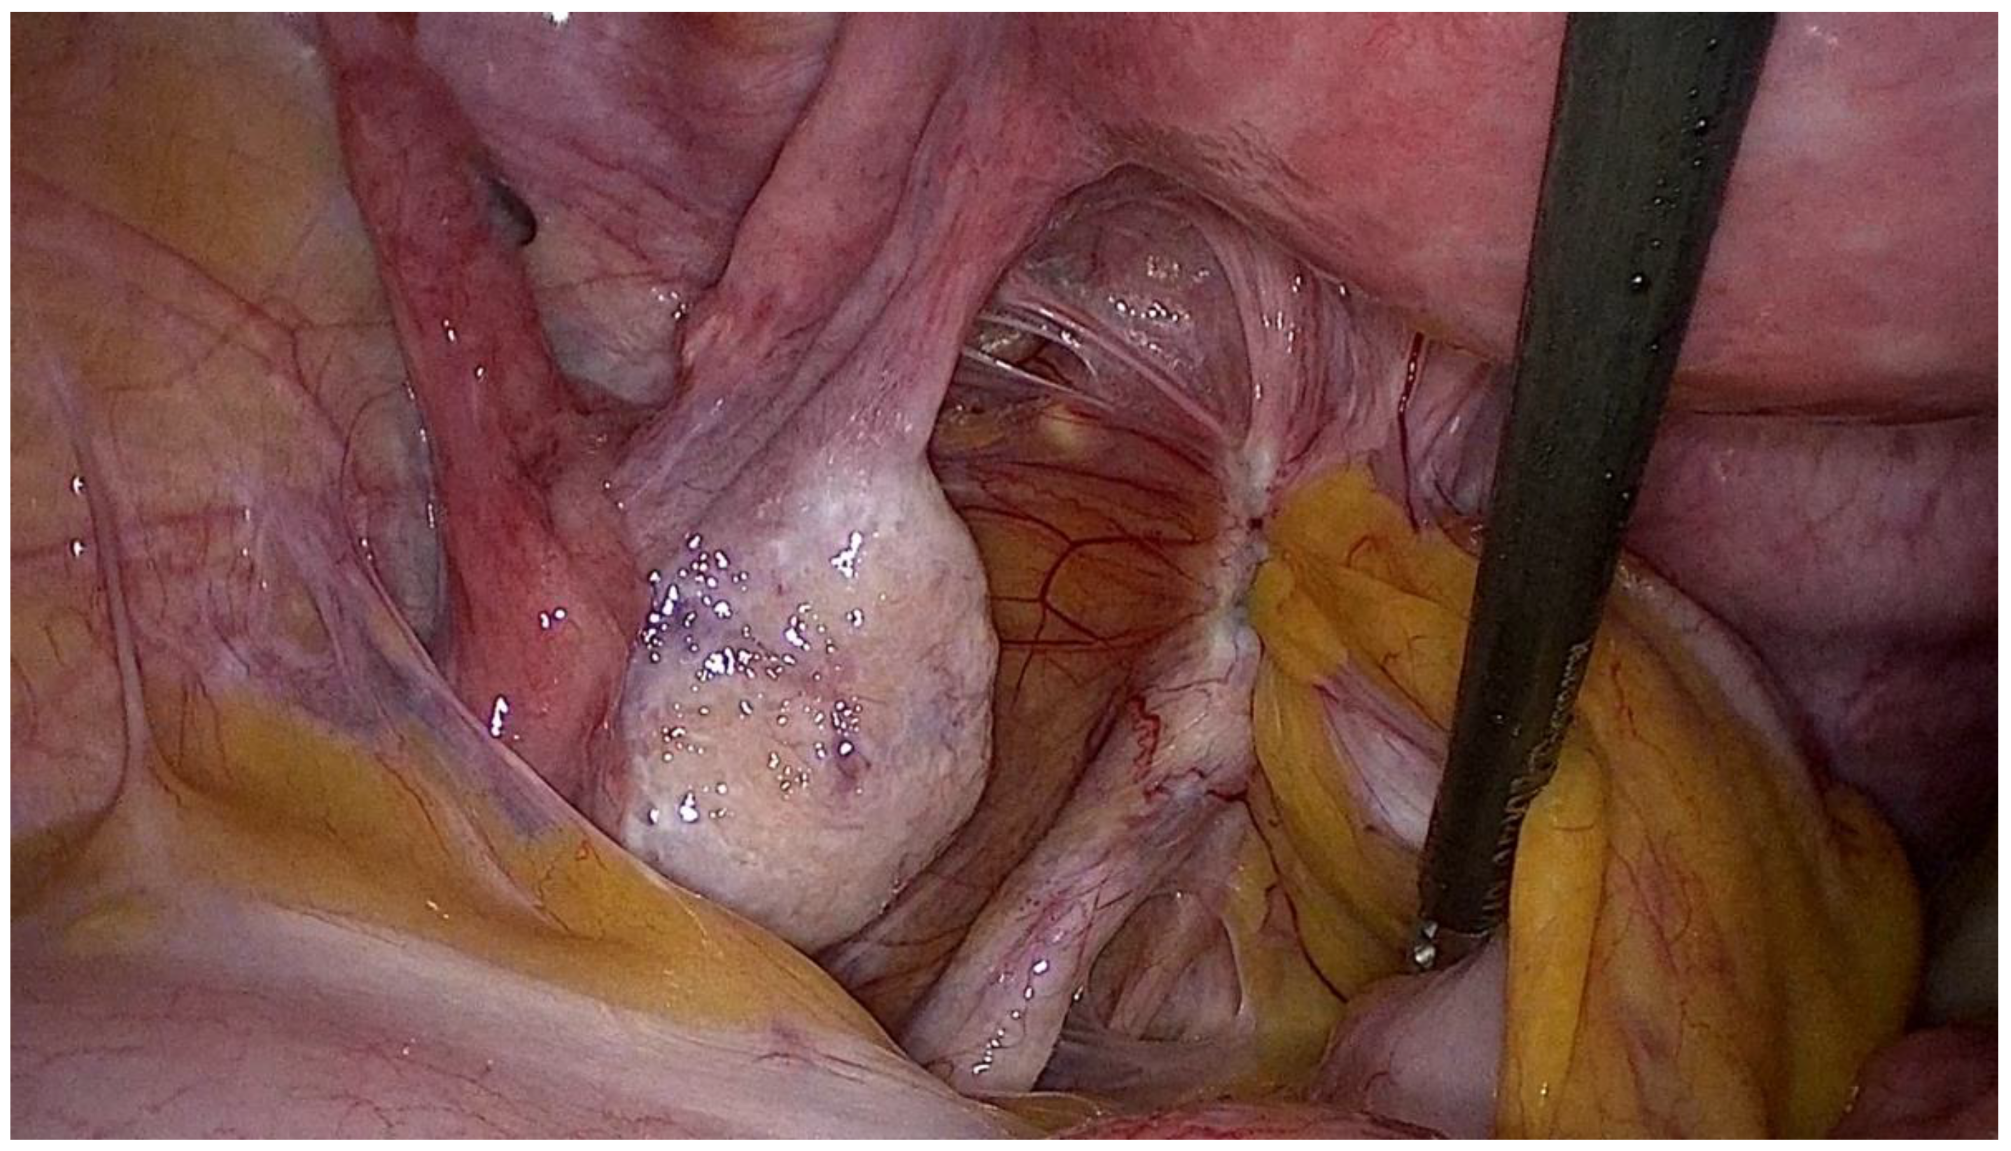

- Centini, G.; Afors, K.; Alves, J.; Argay, I.M.; Koninckx, P.R.; Lazzeri, L.; Monti, G.; Zupi, E.; Wattiez, A. Effect of Anterior Compartment Endometriosis Excision on Infertility. JSLS 2018, 22, 2018.00067. [Google Scholar] [CrossRef] [PubMed]

- Martire, F.G.; Russo, C.; Selntigia, A.; Siciliano, T.; Lazzeri, L.; Piccione, E.; Zupi, E.; Exacoustos, C. Transvaginal ultrasound evaluation of the pelvis and symptoms after laparoscopic partial cystectomy for bladder endometriosis. J. Turk. Ger. Gynecol. Asso. 2022, 23, 145–153. [Google Scholar] [CrossRef] [PubMed]

- Soriano, D.; Bouaziz, J.; Elizur, S.; Zolti, M.; Orvieto, R.; Seidman, D.; Goldenberg, M.; Eisenberg, H.V. Reproductive Outcome Is Favorable After Laparoscopic Resection of Bladder Endometriosis. J. Minim. Invasive Gynecol. 2016, 23, 781–786. [Google Scholar] [CrossRef] [PubMed]